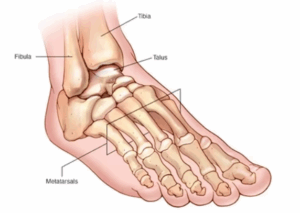

Broken Ankle

A broken ankle, also called a fractured ankle, is an injury of one or more of the bones that make up the ankle joint. An ankle might break from a twisting injury, a misstep or fall, a sports injury or a car crash.

Broken foot

A broken foot, also called a fractured foot, is an injury to one or more bones in the foot. A bone might break from a sports injury, a car crash, a heavy object dropped on the foot, or a misstep or fall.